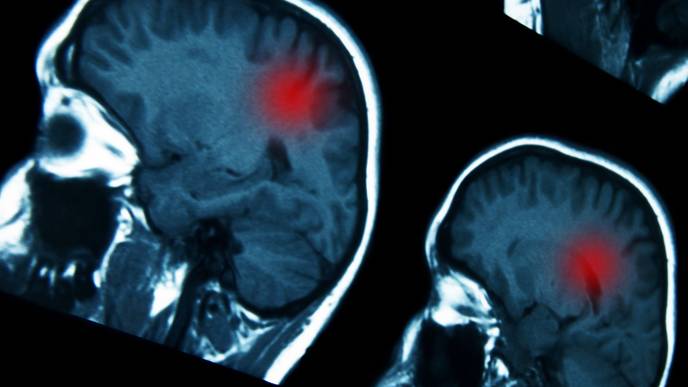

New Review Explores Zika Virus as a Potential Treatment for Brain Cancer

As highlighted in the introduction of this review, many studies have identified oncolytic viruses as a promising new class of therapeutic agents for central nervous system (CNS) tumors, particularly glioblastomas (GBM). Zika virus (ZIKV) proteins, specifically targeting certain stem cells, have shown promising results in both in vitro and animal model studies.

The 14 studies demonstrated that ZIKV reduced cell viability, inhibited the growth and proliferation of glioma stem cells (GSCs), and decreased Bcl2 expression, potentially enhancing chemotherapy and radiotherapy effects. ZIKV caused cytopathic effects, induced tumor cell damage, showed oncolytic properties, and selectively killed GSCs safely. This ultimately led to significant tumor remission and improved long-term survival through an enhanced T-cell response.